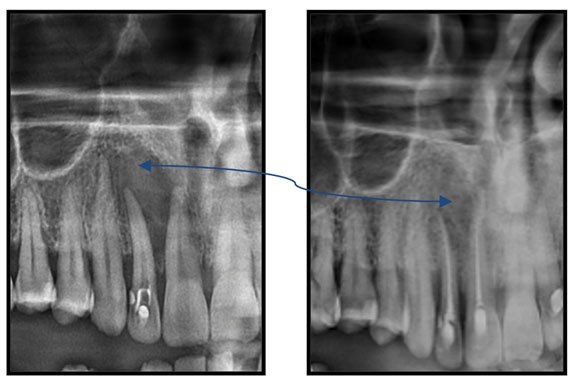

Ατελής ενδοδοντική θεραπεία που οδήγησε σε περιακρορριζική καταστροφή.

Η επανάληψη της ενδοδοντικής θεραπείας δεν οδήγησε σε πλήρη επούλωση της βλάβης,

καθώς είναι αναγκαία και η περιοδοντική θεραπεία του δοντιού.

Χρόνια φλεγμονώδης περιακρορριζική βλάβη, κυρίως,

λόγω ενδοδοντικής αιτιολογίας. Μετά την ενδοδοντική θεραπεία

ακολούθησε περιοδοντική θεραπεία.

Δύο χρόνια μετά, παρατηρείται πλήρης εξαφάνιση της βλάβης.